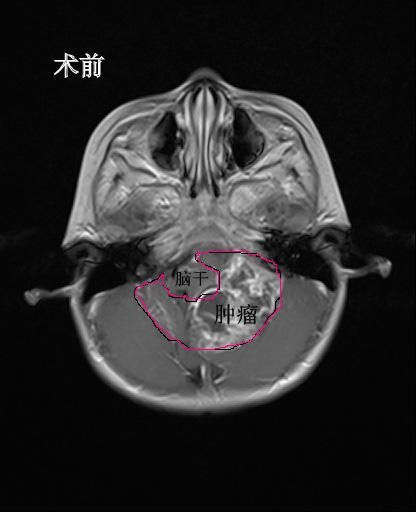

心急如焚的家长急忙将孩子送到温医大育英儿童医院儿童内科就诊。接诊的儿科医生检查发现,孩子的呼吸道疾病表现并不是很严重,反而是全身不适症状明显,精神状态不佳,考虑可能是头颅占位性病变,于是给俊俊做了脑部CT和核磁共振。检查的结果着实让人大吃一惊,年仅2岁多的俊俊后脑竟长了个7cm*5cm*6.5cm,足足有鹅蛋大小的肿瘤。这一结果吓坏了俊俊一家人。孩子从小生长发育都很正常,以前也没有出现过长期头痛的症状,知道孩子颅内长了肿瘤,家里人很难接受。当天,俊俊就被迅速转送到了儿童神经外科。

术前MR检查发现后颅窝巨大占位,脑干被肿瘤包绕

“图像报告显示这颗巨大的肿瘤紧紧包住了四分之三的脑干和好几条神经血管,手术风险极大。我们都知道脑干维持个体生命,包括心跳、呼吸、消化、体温、睡眠等重要生理功能,是人体的生命中枢,稍有不慎就可能造成无法挽回的损失。但这还不是当务之急,”林坚主任说,“迫在眉睫的是肿瘤堵塞了脑脊液的循环通路,造成了大量的脑积水,如不及时处置,不但肿瘤切除手术没法做,孩子随时都有呼吸骤停甚至死亡的可能,必须马上实施脑室外引流术。”